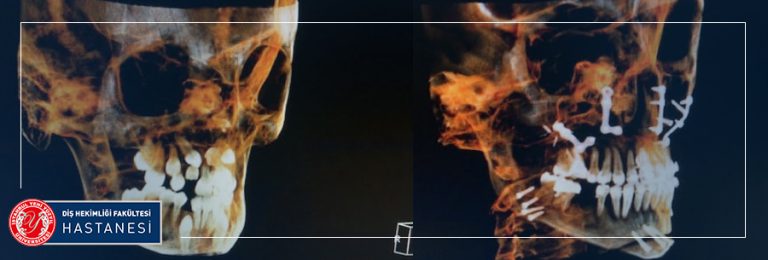

Hastaların fakülteye ilk başvurularında muayenelerinin yapıldığı bölüm Ağız Diş ve Çene Radyolojisi bölümüdür. Ağız, Diş ve Çene Radyolojisi’ne bağlı Oral Diagnoz bölümümüzde; tüm dişler ve ağız içi dokular değerlendirilir. Henüz şikayet olmayan dişlerle ilgili müdahaleler gerekiyorsa, bilgilendirme yapılmaktadır. Hastalıkların teşhis ve tedavilerinde genellikle görüntülenmesi de gerekli olmakta ve bu görüntüleme yöntemleri ve ayrıca diğer kliniklerin ihtiyacı olan radyografi ihtiyaçları da Radyoloji kliniğimizde karşılanmaktadır. Çekilen radyograflar; Gözle yapılan muayenede farkedilmeyen çürük alanlarının, Dolgu altında gelişen yeni çürüklerin, Hijyenik olmayan restorasyonların araştırılmasında, Dişeti hastalıklarında kemik kaybının derecesinin belirlenmesinde, Kanal tedavilerinin başında ve sürecinde, İmplant uygulamalarında kemiğin araştırılmasında, Ortodontik tedavilerin başında ve sürecinde, Çocuklarda diş gelişim ve büyümesinin izlenmesinde, Kemik dokuda ki kist, tümör gibi patolojilerin belirlenmesinde yardımcıdır. Gerekli görüldüğünde ileri görüntüleme ve tetkikler için Tıp hekimliği branşlarından faydalanılmaktadır. Bu bilgilerin ışığında bireye özgü tedavi planı hazırlanmakta ve bu tedavilerin yapılacağı uzman kliniklere hastalar yönlendirilmektedir